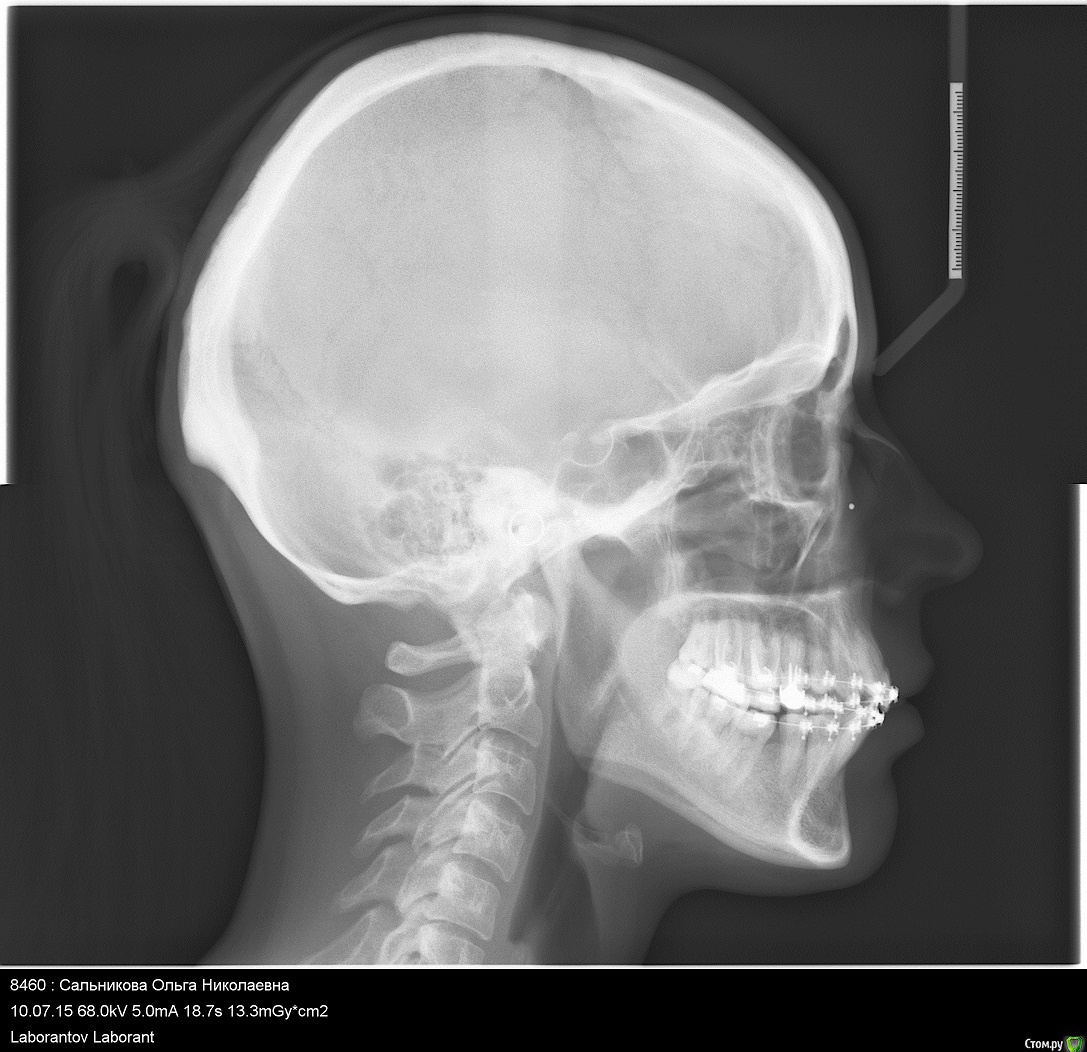

on1976 Опубликовано 18 июля, 2019 Поделиться Опубликовано 18 июля, 2019 (изменено) Добрый день!У меня огромная проблема,Я попала в чудовищную ситуацию в лечении зубов брекетами и вот это длится уже 4 года.По итогу на сегодняшний день, у меня проблемы со здоровьем, депрессия, очень изменилось лицо и прочие последствия.Случайно наткнулась на статьи о "ALF ортодонтия" и прочла об основателе ортокраниодонтии и данного метода в России Алексее Олеговиче Савинове, Skip, но найти информацию и записаться на приём я нигде не могу. А мне важно его мнение по моей ситуации. Сил моих уже больше нет лечиться поскольку улучшений нет. Помогите найти координаты и записаться на приём Савинову.Я прикрепляю файлы ренгена. Может кто выразит своё мнение. (приложенные сними на начальном этапе лечения, сейчас изменения есть, но общая картина изменилась в худшую сторону.)Ортокраниодонтия как последняя надежда! Буду благодарна если получу от вас обратную связьмой тел 89272818180e-mail: on1976@yandex.ru С уважением Сальникова Ольга. Изменено 18 июля, 2019 пользователем on1976 Ссылка на комментарий

Force Опубликовано 20 июля, 2019 Поделиться Опубликовано 20 июля, 2019 Ортокраниодонтия - это альтернативная ортодонтия, то есть по факту - те же возможности, но другими методиками. В вашем случае прямые показания к ортогнатической хирургии. В Астрахани есть хороший ортодонт - пишите в личку Ссылка на комментарий

on1976 Опубликовано 23 июля, 2019 Автор Поделиться Опубликовано 23 июля, 2019 Ортокраниодонтия - это альтернативная ортодонтия, то есть по факту - те же возможности, но другими методиками. В вашем случае прямые показания к ортогнатической хирургии. В Астрахани есть хороший ортодонт - пишите в личкуТак -то оно так, но в течении 4 лет ношения брекетов, положение стало меняться, и я задумалась о возможности решения альтернативным способом, перекос верхней части стал меньше. Возможно это можно решить ALF капой? Ссылка на комментарий